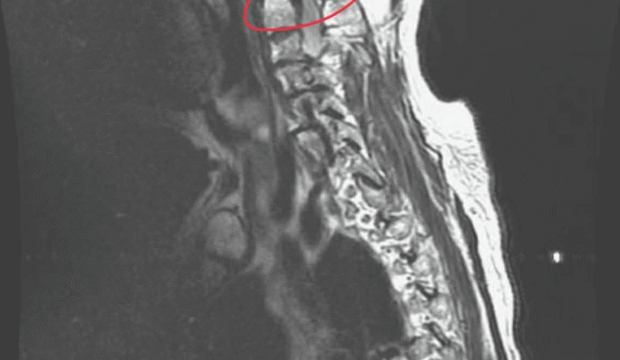

當脊椎的神經受到壓迫刺激時,會導致對應的神經根出現症狀。這症狀可能是麻、可能是痛、也可能是無力。當此狹窄非常嚴重與極端狀況時,可能導致大小便失禁等狀況。所以脊椎手術的成功,很大一部份有賴非常良好的神經減壓。但具體來說,神經被壓迫刺激,是被甚麼壓迫呢?這就是臨床上要判斷的,可能是突出的椎間盤、可能是發炎增厚的韌帶關節囊等軟組織、也可能是鈣化的組織或者日積月累養出的退化骨刺當他們正好在神經的路徑上時,就可能會是神經壓迫的元凶。所以,所謂脊椎神經減壓手術,不外乎要把這些組織與神經分離,讓神經不再被壓迫刺激。這部份我們可以統稱叫做:神經減壓。

這個術式叫做-椎間孔入路腰椎椎體間融合術(TLIF)。他是一種經常以微創手術(MIS)方式進行的脊椎融合手術。可藉由此手術恢復椎間盤高度,並融合下背部受損骨折過或滑脫的椎體。不同於開放手術,微創TLIF方法允許透過背部一個小切口進入腰椎,通過輕柔分離周圍肌肉而不是切割它們,從而最小化肌肉和軟組織的破壞。與傳統的手術方法相比,這種程序通常對身體的創傷和破壞更小,並且通常允許患者更快恢復。

TLIF的目的是通過恢復椎間盤高度的間接以及搭配直接的神經減壓並融合椎體來穩定脊椎,從而增強脊椎穩定性並緩解神經壓迫。